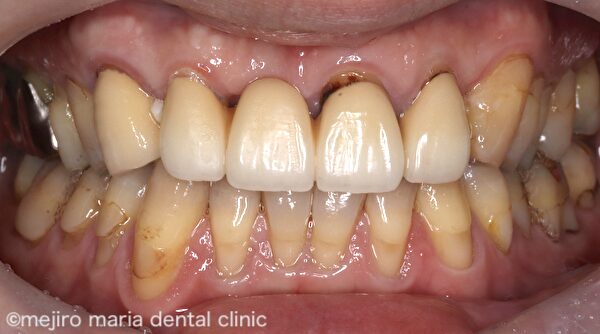

患者様は現在装着中の前歯のブリッジの見た目が悪いという点と、食べ物が詰まって困るという2点を主訴に受診されました。

右上3〜左上2までのブリッジが装着されており、欠損部である右上1の歯肉は大きく凹んでしまっています。また、歯肉に対して適合の悪いブリッジが作製されており、歯肉には著明な炎症所見が認められます。この状態では適切に清掃を行い健康な歯肉を維持することはできないでしょう。

歯肉形態を改善させ、機能的、審美的に満足のいくブリッジ治療を行うことにしました。